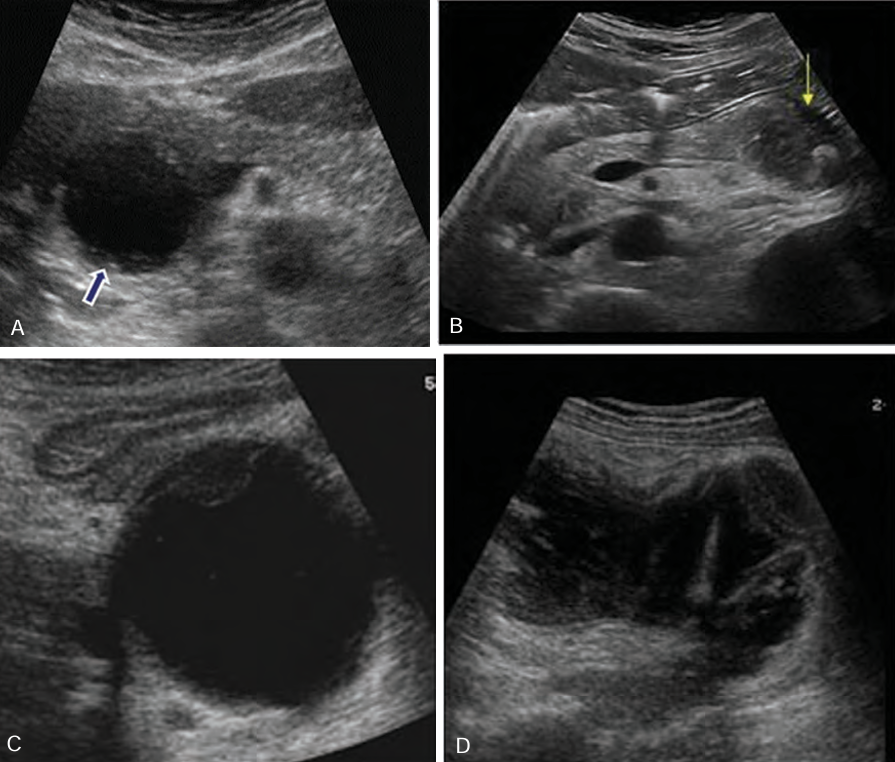

Sonographically, hemorrhagic pancreatitis depends on the ____ of the hemorrhage

age

Sonographically, a ______ necrosis may be seen as a ___- defined, ________ mass in the area of the pancreas

fresh; well; homogenous

Sonographically, at ____ week, the mass (hemorrhage) may appear ____ with ____ elements or _______

1; cystic; solid; septation

Sonographically, after _____ weeks, the hemorrhage may appear ______

several; cystic

Hemorrhagic pancreatitis is a rapid progression of ______ pancreatitis with _______ of pancreatic ______ and subsequent __________

rapid; acute; rupture; vessels; hemorrhage

In _______ pancreatitis, there is diffuse _____ destruction of the pancreatic substance caused by a sudden escape of ______ pancreatic ________ into the ______ parenchyma

hemorrhagic; enzymatic; active; enzymes; glandular